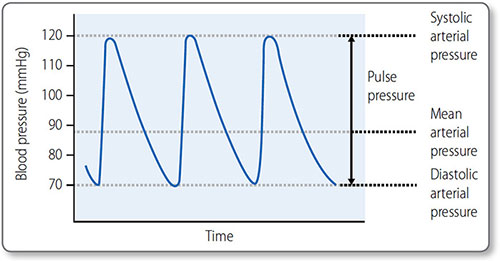

Blood pressure

Figure 1.34: Systolic, diastolic and mean arterial blood pressure. The pulse pressure is the difference between the systolic pressure and the diastolic pressure.

Blood pressure is expressed as the systolic value over the diastolic value, for example 120/80 mmHg. Mean arterial pressure (MAP) is the average blood pressure over the period of the cardiac cycle (Figure 1.34).

57Maximum blood pressure is reached during systole, and the minimum occurs in diastole. Although the heart is an intermittent pump, blood pressure is maintained during diastole by elastic recoil of the large arteries (Figure 1.35). Blood pressure declines the more distal a vessel is from the left ventricle, as flow energy is lost via friction and resistance decreases.